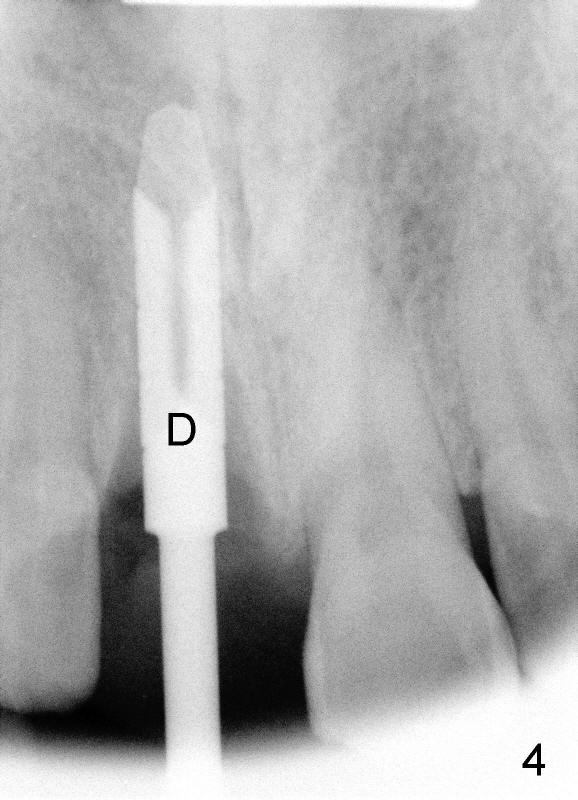

A 55-year-old man has severe pain on the upper right central incisor (Fig.1 *) after biting on a piece of bone. PA confirms crown fracture (Fig.2 <), extending subgingivally (Fig.3 >>). Osteotomy forms using a 2 mm pilot drill and 2.5-3.5 mm reamers (Fig.4). A 5x17 mm Tatum tapered implant is placed, autogenous bone placed in the buccal gap, sutures placed for wound approximation and 3.5 mm 20º angled abutment installed (Fig.5). An immediate provsional is fabricated (Fig.6), cemented and splinted (Fig.7).,